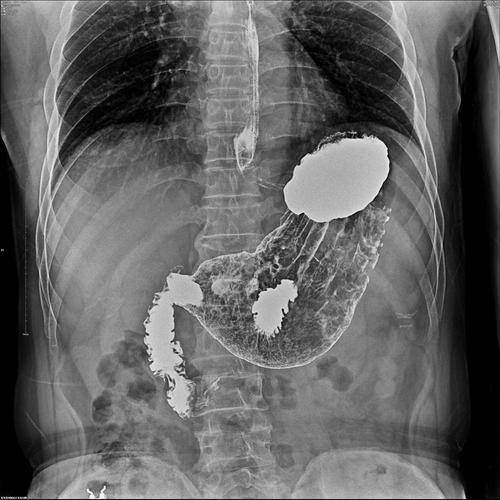

上消化道造影检查技术及常见病变的x线诊断

上消化道造影图片讲解

消化道造影